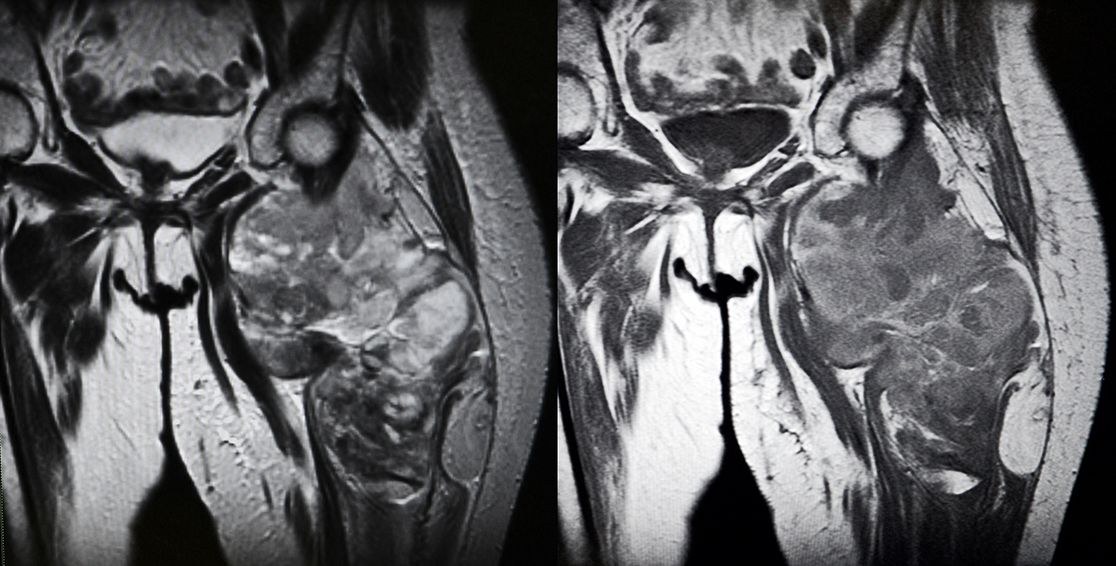

Grundlage der Diagnose ist zunächst eine Befragung des Patienten (Anamnese) nach Vorerkrankungen und Symptomen sowie eine sorgfältige körperliche Untersuchung. Bei auffälligen Tastbefunden können durch eine Ultraschalluntersuchung (Sonographie) und/oder Röntgenbilder erste Hinweise auf Vorliegen eines Tumors erkannt werden. Sollte der Verdacht auf ein Sarkom bestehen, dann werden weitere bildgebende Verfahren angewendet, wie zum Beispiel Magnetresonanztomographie (MRT), Computertomographie (CT) oder in Einzelfällen bei machen Subtypen auch eine Positronenemissionstomographie (PET-CT bzw. PET-MRT).